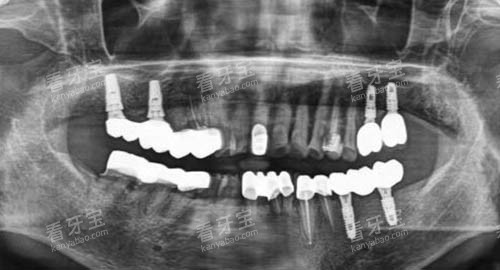

沈阳国民口腔门诊部紧跟口腔医学发展的步伐,引进了一系列新型的口腔诊疗设备。

例如,智能化口腔全景机能够快速、较准地拍摄口腔全景图像,为医生提供齐全、清晰的口腔状况信息,有助于制定更加比较准的治疗方案。

此外,门诊部还配备了新型的种植系统,其种植精度高、结果好,大大提高了种植牙的成功几率和稳定性。